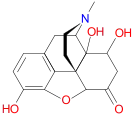

Others

- 1-Nitroaknadinine * 14-episinomenine

- 5,6-Dihydronorsalutaridine

- 6-Keto Nalbuphine

- Aknadinine

- Butorphanol

- Cephakicine

- Cephasamine

- Cyprodime

- Drotebanol

- Fenfangjine G

- Ketorfanol

- Nalbuphine

- Nalbuphone

- Tannagine

Structures

| Other Morphinans | ||||

|---|---|---|---|---|

1-Nitroaknadinine 1-Nitroaknadinine |

14-episinomenine 14-episinomenine |

5,6-Dihydronorsalutaridine 5,6-Dihydronorsalutaridine |

6-Keto Nalbuphine 6-Keto Nalbuphine |

Aknadinine Aknadinine |

Butorphanol Butorphanol |

Cephakicine Cephakicine |

Cephasamine Cephasamine |

Cyprodime Cyprodime |

Drotebanol Drotebanol |

Fenfangjine G Fenfangjine G |

Nalbuphine Nalbuphine |

Sinococuline Sinococuline |

Sinomenine Sinomenine |

Tannagine Tannagine |